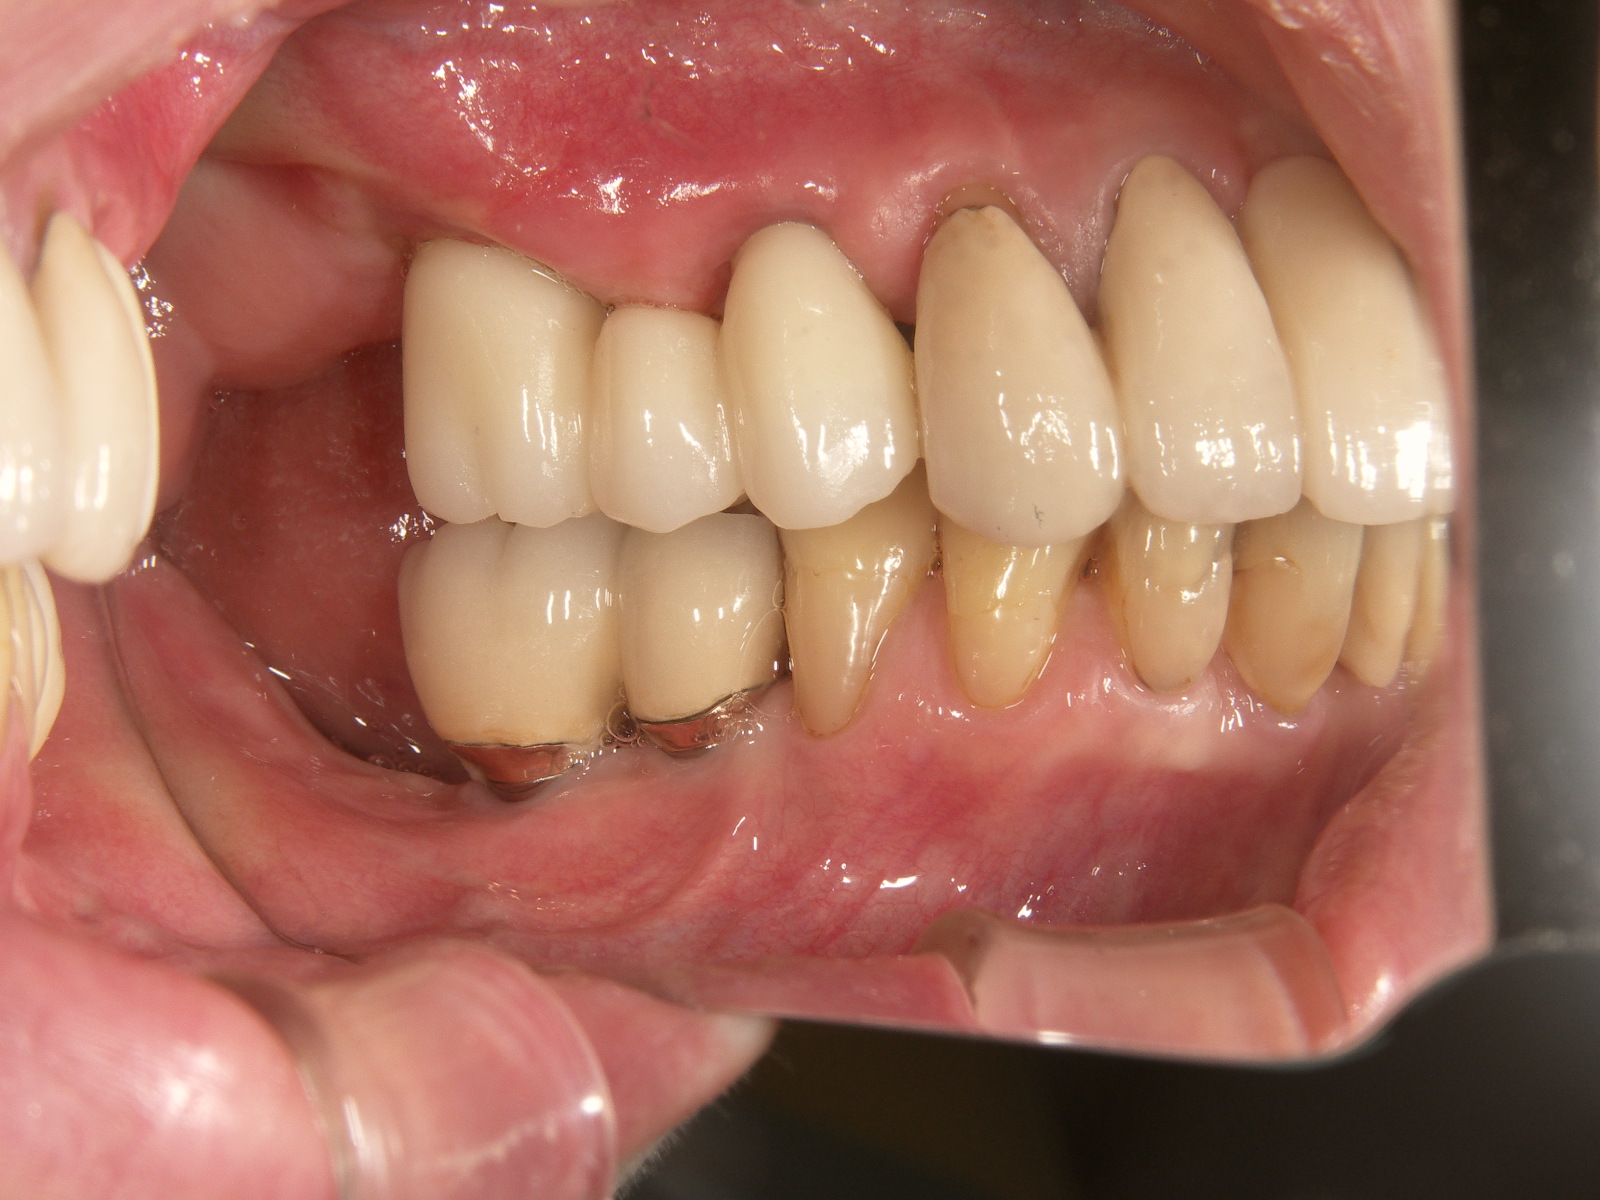

インプラント施術前

下あごの奥歯がなく、食いしばりが強いため前歯もすり減ってしまいました。

インプラント施術後

インプラントを6本埋入してかみ合わせも適当な高さに改善、前歯もセラミックをかぶせて見た目も改善しました。